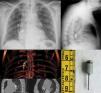

The patient came to the Emergency Department from a dental appointment one hour earlier, during which a drill bit had accidentally fallen into his oral cavity while he was undergoing root canal treatment, and disappeared; the dentist believed that the patient had swallowed it, and referred him to our hospital. The patient was asymptomatic on arrival. Chest X-ray and computed axial tomography (CT) (Fig. 1) revealed the drill bit in the bronchus intermedius, with no associated complications. Oral bronchoscopy was performed under sedation, and the bit was removed en bloc using crocodile forceps (Fig. 1). The patient was discharged 24h later.